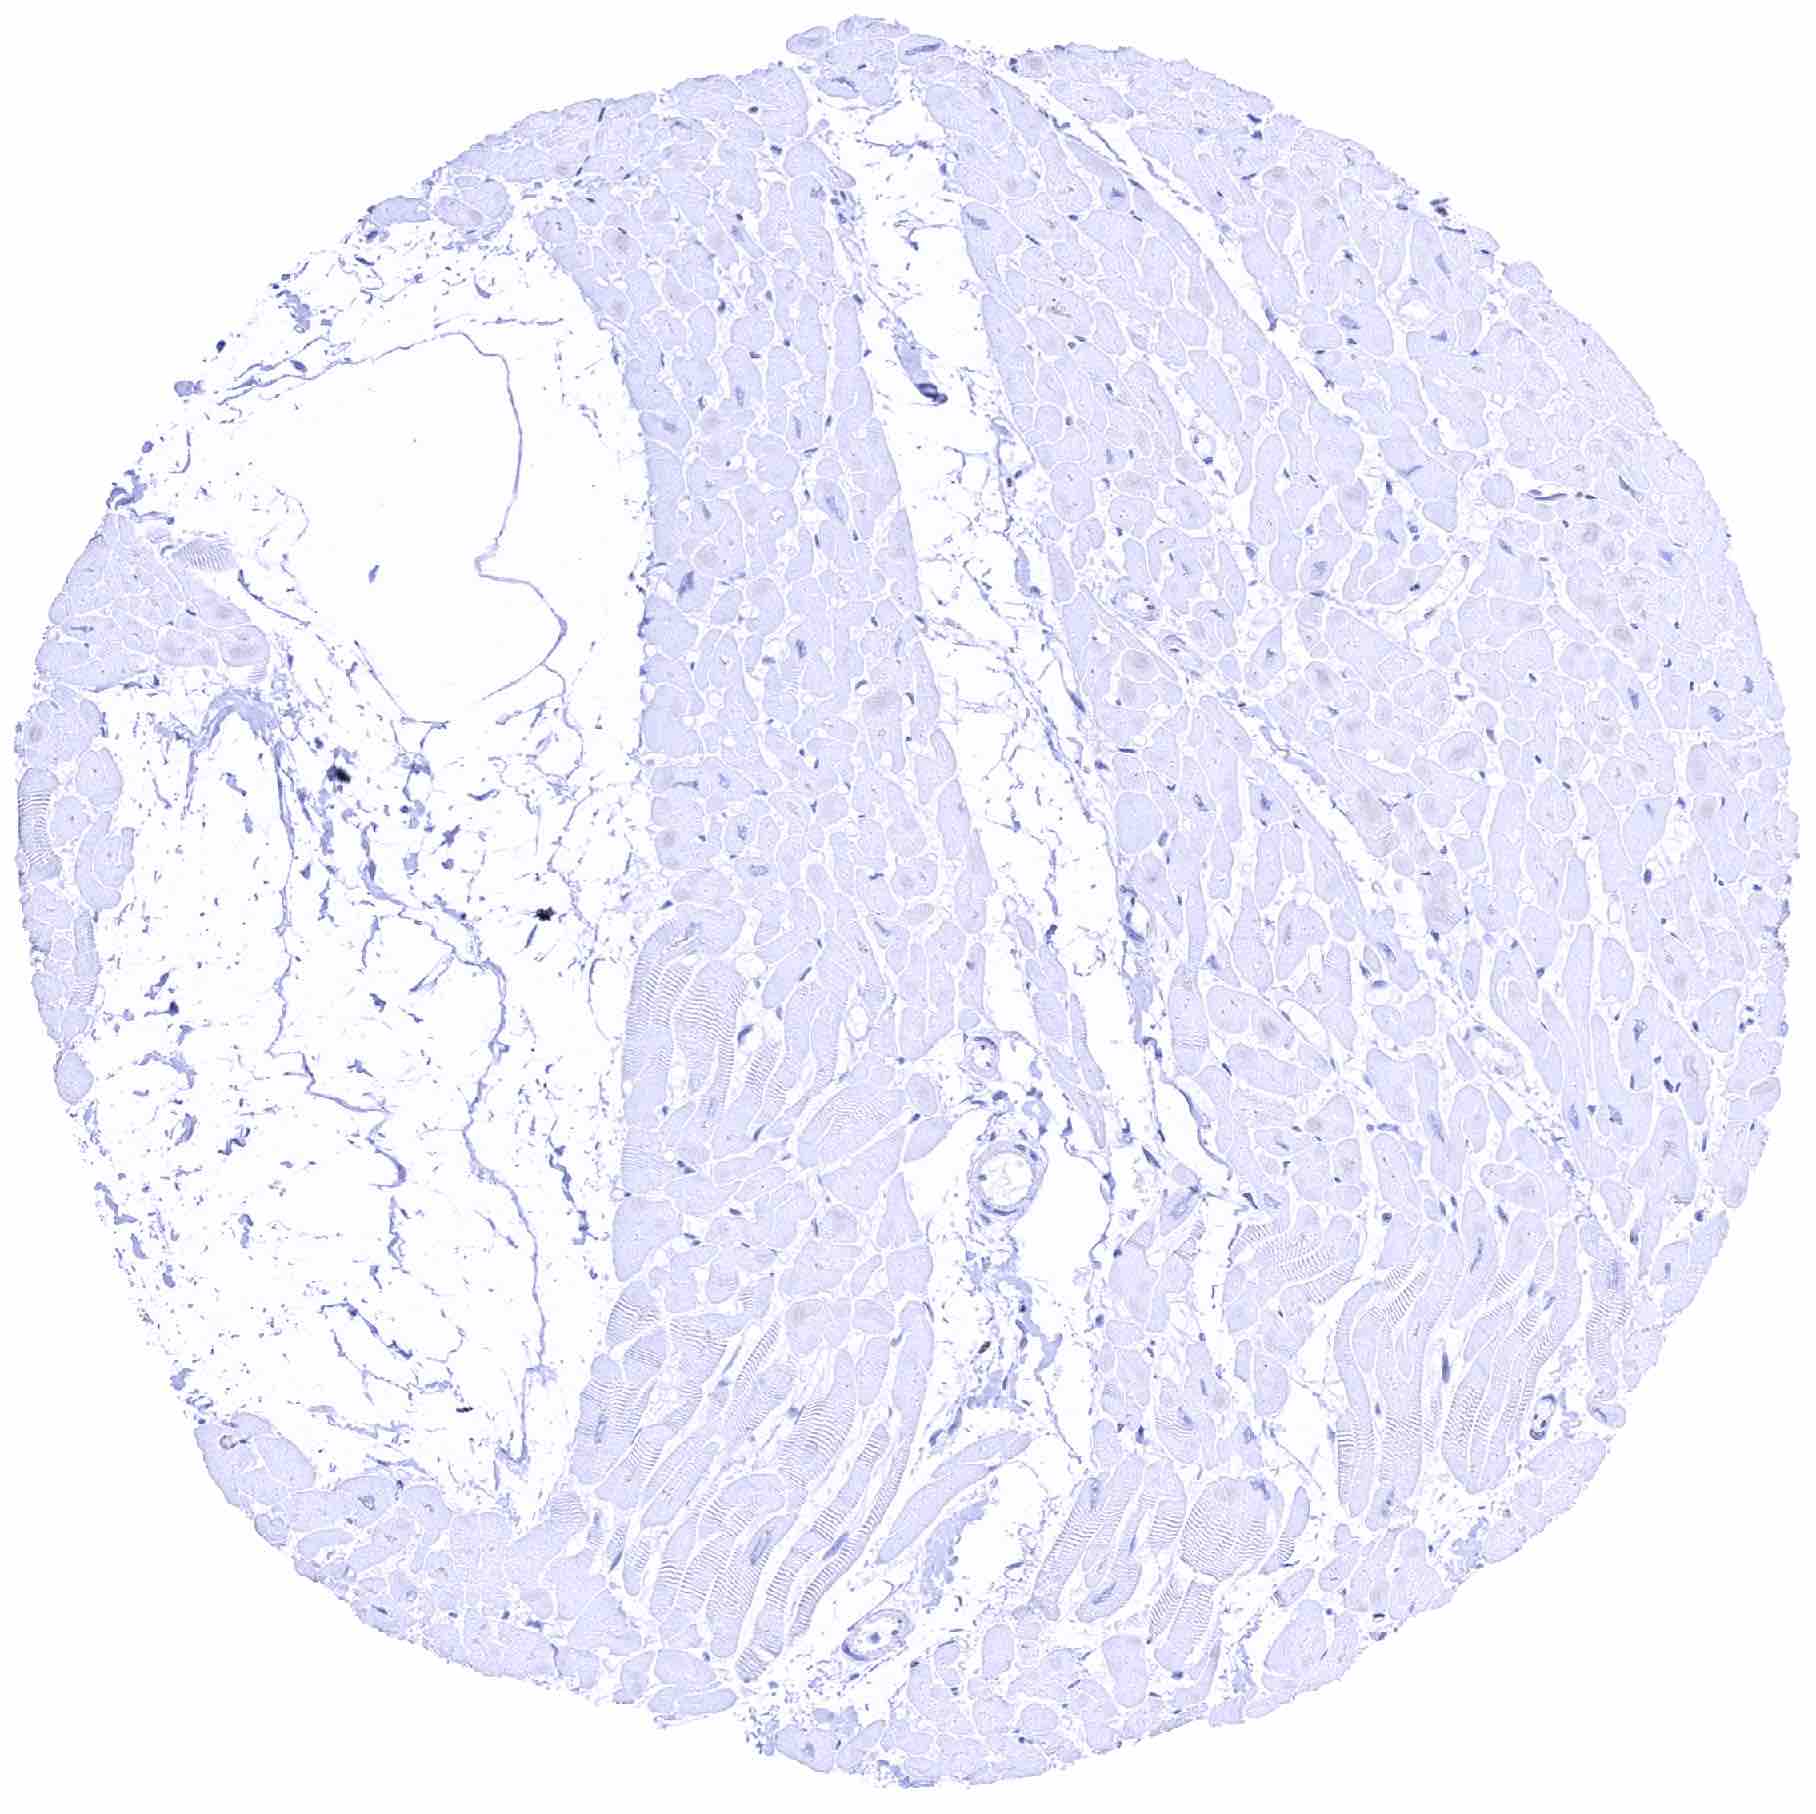

Heart muscle

Skeletal muscle